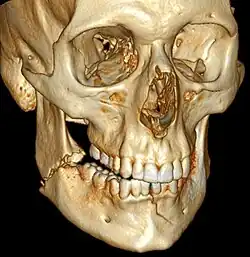

3D CT reconstruction of mandible fracture, white arrow marks fracture, red arrow marks moderate displacement and open bite -